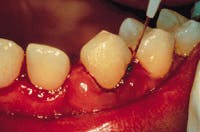

During pretreatment, five diagnostic tests were run. The clinical examination was done on a 56-year-old female. The tooth vitality was all within normal limits, and hard tissue tests showed broken-down dentition. The radiographic exams revealed moderate and generalized horizontal bone loss, as well as recurrent caries around restorations. Tests on the soft tissue displayed inflammation, calculus, 5-6 mm pockets, and bleeding on probing (see Figure 4).

The diagnosis was Type III moderate periodontitis. Treatment involved scaling and root planing using microultrasonics and sulcular debridement. Possible treatment alternatives included surgery with no laser instrumentation. The indications were inflammatory tissue and diseased epithelial lining of the pockets.

The treatment objective was to restore periodontal health via laser operating parameters of 30mJ, 60Hz, 1.8W, 30 to 60 seconds per pocket, followed by microultrasonic instrumentation, then 100mJ, 20Hz, 2.0W, 30 to 60 seconds per pocket. The treatment sequence was weekly appointments of one-hour duration for a total of six hours. The laser was used for 10 minutes during the one-hour appointment.

The laser fiber was calibrated for the pocket depth and was placed at the top of the sulcus. The fiber was held parallel to the root surface, but always kept on the diseased tissue. The fiber was moved both horizontally and vertically. Diseased tissue was removed by withdrawing the fiber. No complications were experienced. The diseased epithelial tissue was easily removed with excellent hemostasis. Patient management was excellent with topical anesthesia only.

Figure 4 Results of periodontal charting at clinical exam for 56-year-old female.

Figure 5 Results of periodontal charting after laser therapy.